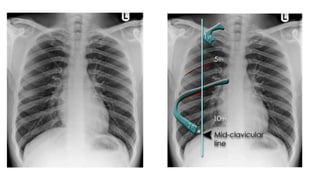

This document discusses key aspects of thorax radiology including positioning for PA and AP views, assessing heart size, visibility of anatomical structures like the scapulae, lungs zones, and measurements like cardiothoracic ratio. It provides guidance on evaluating rotation, inspiration, and penetration on chest x-rays as well as identifying structures like the lobe of azygos vein and aortic knuckle.